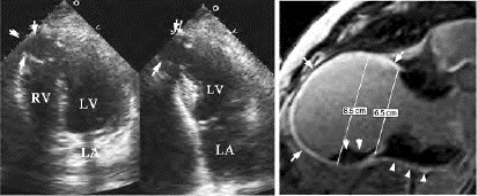

(1)局部室壁呈瘤样向外膨出(图19-12)。

图19-12 室壁瘤二维超声图

左室下壁(左图)、心尖部(右图)室壁瘤,左室下壁中部(左图)、心尖部(右图)室壁变薄,心肌回声增强,局部明显向外膨出